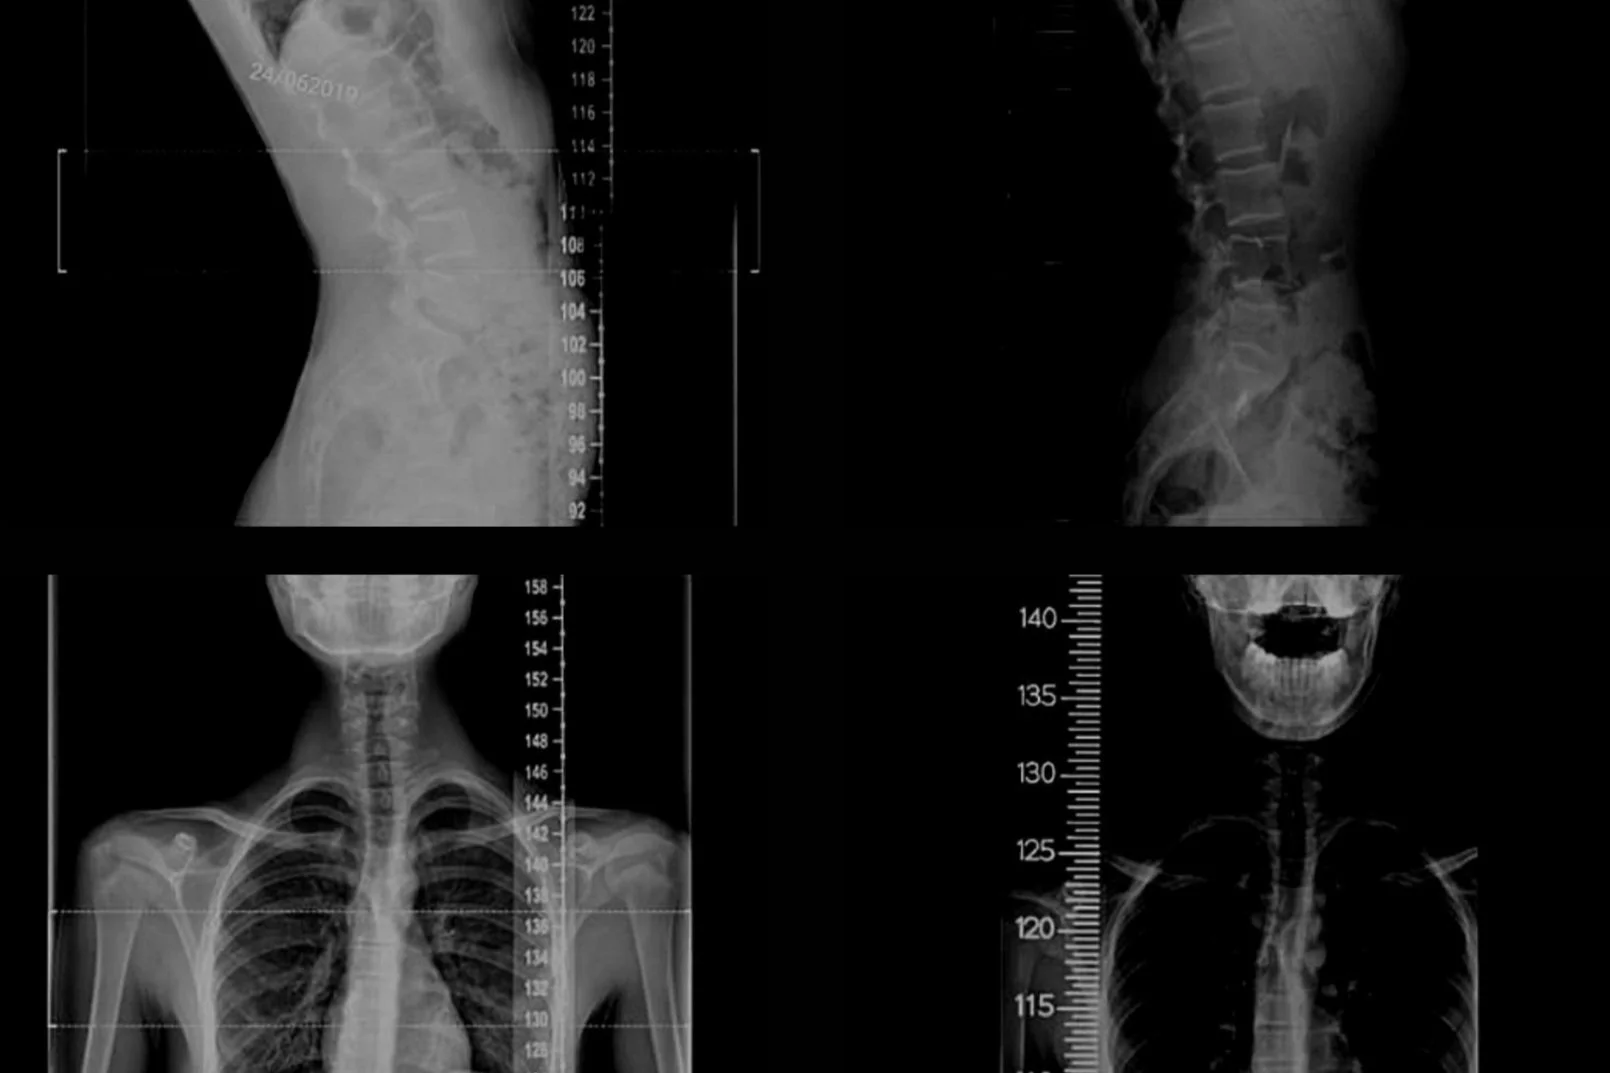

Functional Patterns For Scoliosis Poor movement patterns and muscle imbalances are root causes of scoliosis. In my career of working with people who had a scoliosis somewhat often, i never encountered a case this rigid. Poor movement patterns and muscle imbalances are root causes of scoliosis. Finding nina at fp has been a blessing. Maddie was diagnosed with scoliosis. If you're seeking a natural way to address scoliosis, functional patterns offers a holistic approach that focuses on correcting. Today, i stand as a testament to the transformative power of functional patterns. Conversation with madison mossman sharing her experience with functional patterns. Functional patterns counteract the motions that lead to the large curve by activating the right muscles in the right sequence. I then realized that what i knew at that point was not going to be. Movement patterns and muscle imbalances: